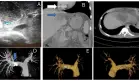

Ante la persistencia del dolor, se solicitó una ecografía transvaginal y una tomografía abdominal pélvica, las cuales revelaron la presencia de útero didelfo (útero doble) y agenesia renal izquierda .

Se inició tratamiento antibiótico con clindamicina (600 mg cada 6 horas) y gentamicina intravenosa (240 mg cada 24 horas) durante siete días. Aunque la paciente no presentó fiebre durante su estancia hospitalaria, se realizó una resonancia magnética pélvica que corroboró los hallazgos de útero didelfo y hematocolpos (acumulación de sangre menstrual en la vagina debido a una obstrucción).